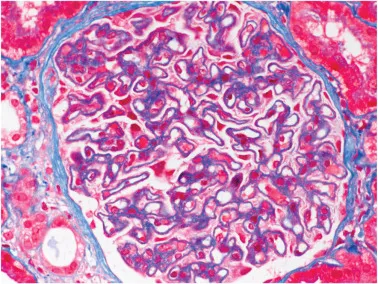

* Nefropatia membranosa (NM): principal protótipo

* Densidade inflamatória > 8 células/glomérulo na biópsia